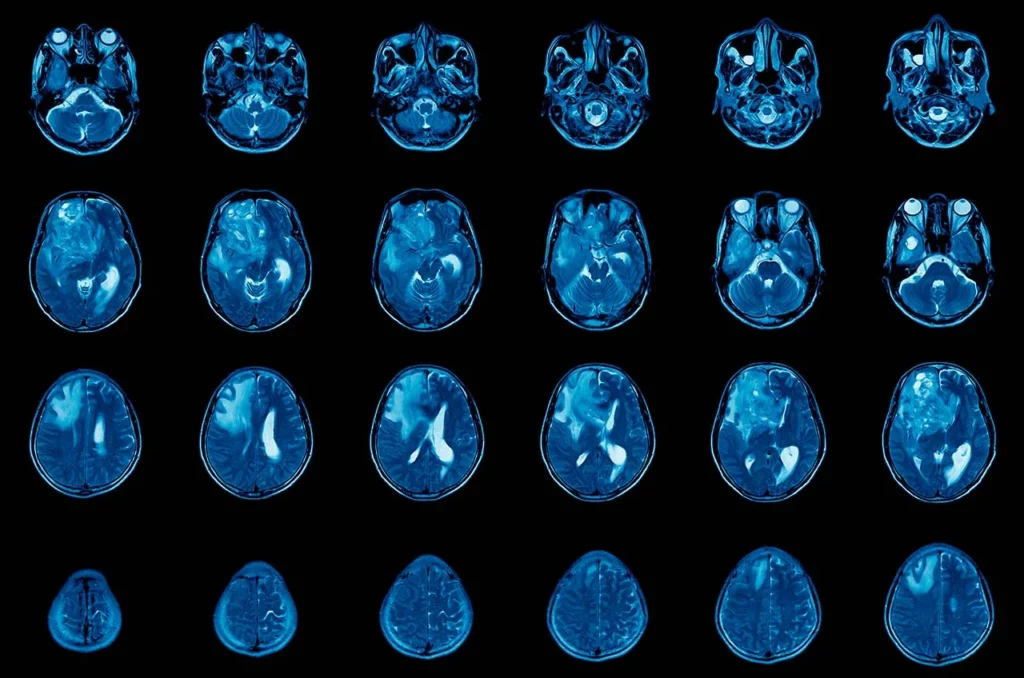

Imágenes de resonancia magnética de un cerebro para analizar la presencia de un glioma multiforme.